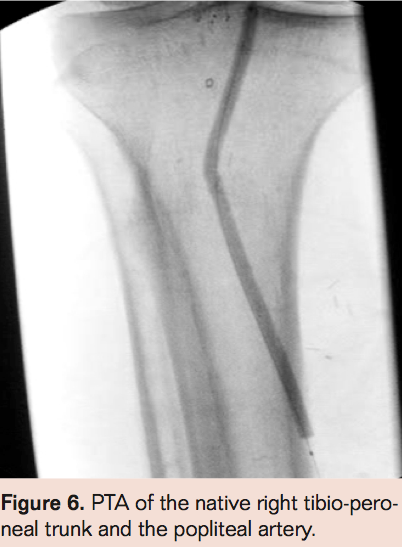

- Cross occlusion with guidewire of choice (must exchange for .014 guidewire if larger wires used to cross) (Figure 2)

- Laser thrombectomy with a 0.9 mm probe advanced 1 mm/sec with saline flush via the sheath (Figure 3)

- Laser thrombectomy at 1 mm/sec. with the 2.3 mm probe (Figures 4-9)